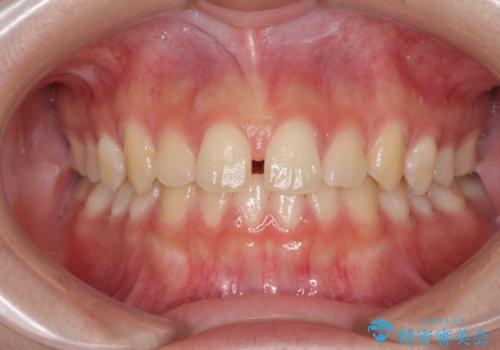

前歯のすきっ歯を治したい インビザラインによる矯正治療

- 上顎前歯の隙間を気にして来院された患者様です。

目立たない装置を希望とのことで、インビザラインを用いて矯正治療を行うこととしました。

最終的には隙間は全て閉じ、綺麗な仕上がりとなりました。